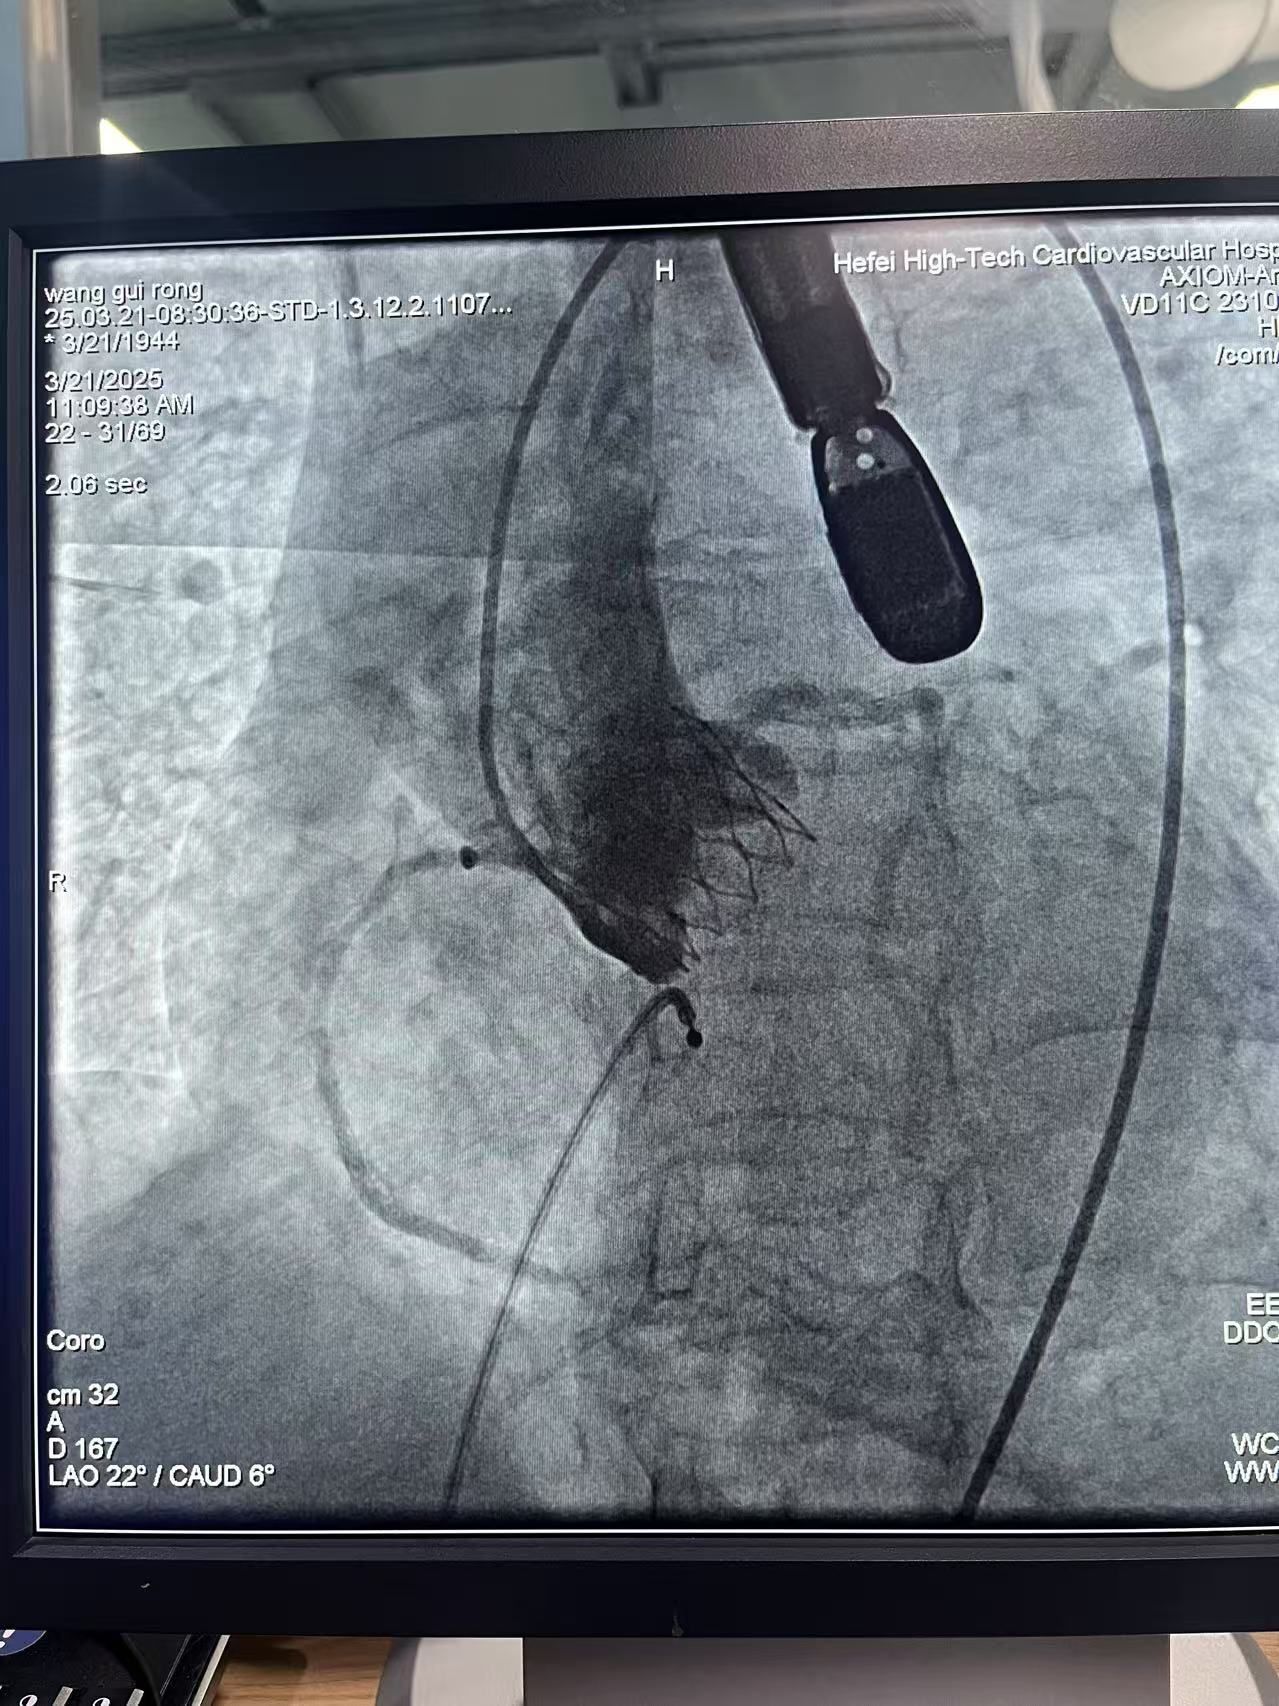

近日,合肥高新心血管病医院梅举院长领衔心胸外科团队取得重大技术突破,成功为一名81岁高龄的主动脉瓣重度狭窄患者实施经导管主动脉瓣置换术(TAVR)。此次手术团队采用了乐普医疗自主研发的新型TAVR产品,标志着该产品正式上市后的安徽省首例临床植入圆满完成,为心脏瓣膜疾病微创治疗再添利器。

患者为81岁老年女性,多年来饱受反复胸闷、气促困扰,心脏彩超显示其主动脉瓣口面积仅0.7cm2,确诊为主动脉瓣重度狭窄。传统开胸手术需要锯开胸骨、建立体外循环,对于这位合并高血压、冠心病等多种合并症的耄耋老人而言风险极高。经多学科评估,梅举院长团队决定采用乐普医疗新一代TAVR系统,通过股动脉穿刺,将人工瓣膜精准输送至心脏病变部位完成置换。手术历时不足2小时,患者术后血流动力学显著改善,不久后便可下床活动,目前恢复良好出院。